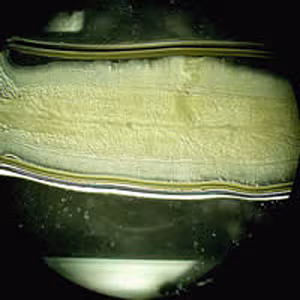

Taenia spp. proglottids.

Separation of T. saginata and T. solium is best accomplished by examination of mature proglottids. Taenia saginata has 12-30 primary lateral uterine branches, while T. solium has 7-13 primary lateral uterine branches. Visualization of the branches can be improved by clearing the specimen in lactophenol followed by India ink injection into the lateral genital pore. The procedure is as follows:

Microscopic identification of eggs and proglottids in feces is diagnostic for taeniasis, but is not possible during the first 3 months following infection, prior to development of adult tapeworms. Repeated examination and concentration techniques will increase the likelihood of detecting light infections. Nevertheless, identification of Taenia is not possible if solely based on microscopic examination of eggs, because all Taenia species produce eggs that are morphologically identical. Eggs of Taenia spp. are also indistinguishable from those produced by cestodes of the genus Echinococcus (tapeworms of dogs and other canid hosts). Microscopic identification of gravid proglottids (or, more rarely, examination of the scolex) allows species determination.